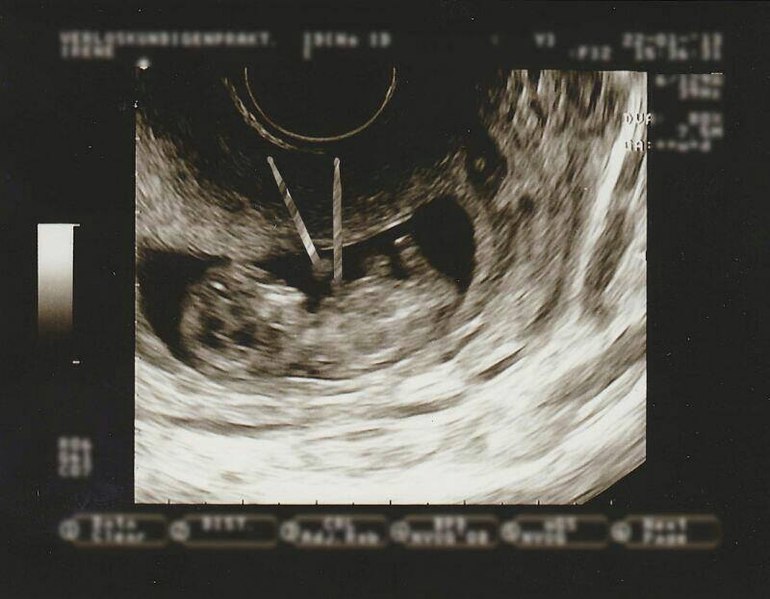

Всегда когда смотрю на фото узи на глазах слезы выступают)

21.06.2013

Аналогично... Жду-не дождусь следующего УЗИ :)